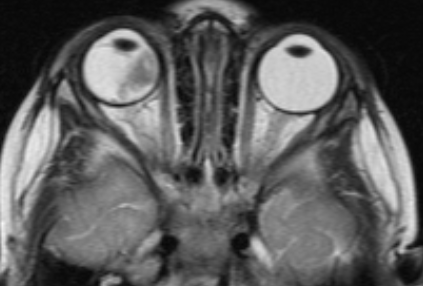

МРТ головного мозга и орбит

Магнитно-резонансная томография дает возможность в деталях увидеть распространение процесса за пределы глазного яблока и точно определить стадию болезни. Такое исследование нужно проводить всем пациентам, у которых ретинобластома диагностирована впервые. Контраст при МРТ повышает информативность.

![Визуализация ретинобластомы с помощью МРТ. Клиническая группа В]()

Рис. 2. Визуализация ретинобластомы с помощью МРТ. Клиническая группа В

![Визуализация ретинобластомы с помощью МРТ. Размеры образования соответствуют клинической группе D]()

Рис. 3. Визуализация ретинобластомы с помощью МРТ. Размеры образования соответствуют клинической группе D

![Визуализация ретинобластомы с помощью МРТ. Фронтальное изображение орбит. Клиническая группа D]()

Рис. 4. Визуализация ретинобластомы с помощью МРТ. Фронтальное изображение орбит. Клиническая группа D